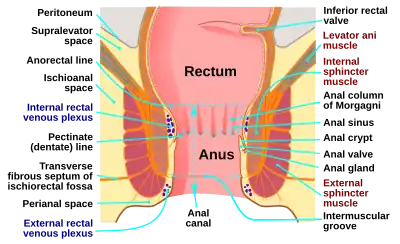

Structure

The anus is the final part of the gastrointestinal tract, and directly continues from the rectum, passing through the pelvic floor. The top and bottom of the anus are surrounded by the internal and external anal sphincters, two muscular rings which control defecation.[6]: 397 The anus is surrounded in its length by folds called anal valves, which converge at a line known as the pectinate line. This represents the point of transition between the hindgut and the ectoderm in the embryo. Below this point, the mucosa of the internal anus becomes skin.[6] : 397 The pectinate line is also the division between the internal and external anus.

The anus receives blood from the inferior rectal artery and innervation from the inferior rectal nerves, which branch from the pudendal nerve.[7]

The pseudostratified columnar epithelium of the gastrointestinal tract transitions to stratified squamous epithelium at the pectinate line. The stratified squamous epithelium gradually accumulates sebaceous and apocrine glands.[8]: 285

Intra-rectal pressure builds as the rectum fills with feces, pushing the feces against the walls of the anal canal. Contractions of abdominal and pelvic floor muscles can create intra-abdominal pressure, which further increases intra-rectal pressure. The internal anal sphincter (an involuntary muscle) responds to the pressure by relaxing, thus allowing the feces to enter the canal. The rectum shortens as feces are pushed into the anal canal and peristaltic waves push the feces out of the rectum. Relaxation of the internal and external anal sphincters allows the feces to exit from the anus, finally, as the levator ani muscles pull the anus up over the exiting feces.